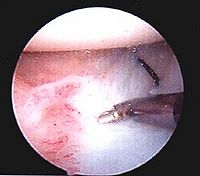

髋关节脱位--X片